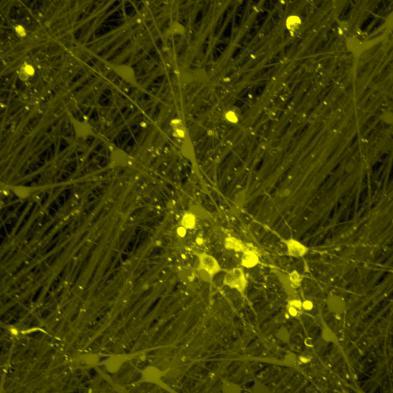

Calceinlabellingofneuron-astrocytecoculturesatmultipletimepointsshowedrobustcellviabilityandincreasedculturecomplexityovertime.

1week7weeks

Calcein